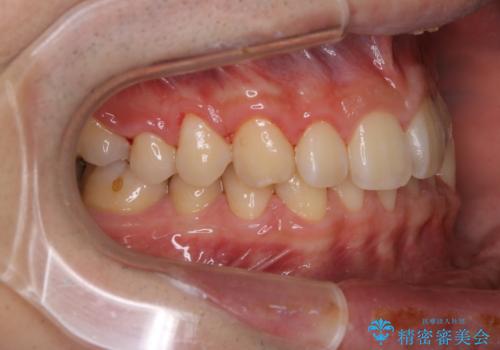

人生で初めてのクリーニングということもあり、プラークや歯石が大量に付いていました。それにより、歯茎の腫れもあり出血も多かったです。これから矯正をスタートしていくため、歯ブラシ指導を行いホームケアを頑張ってもらっています。